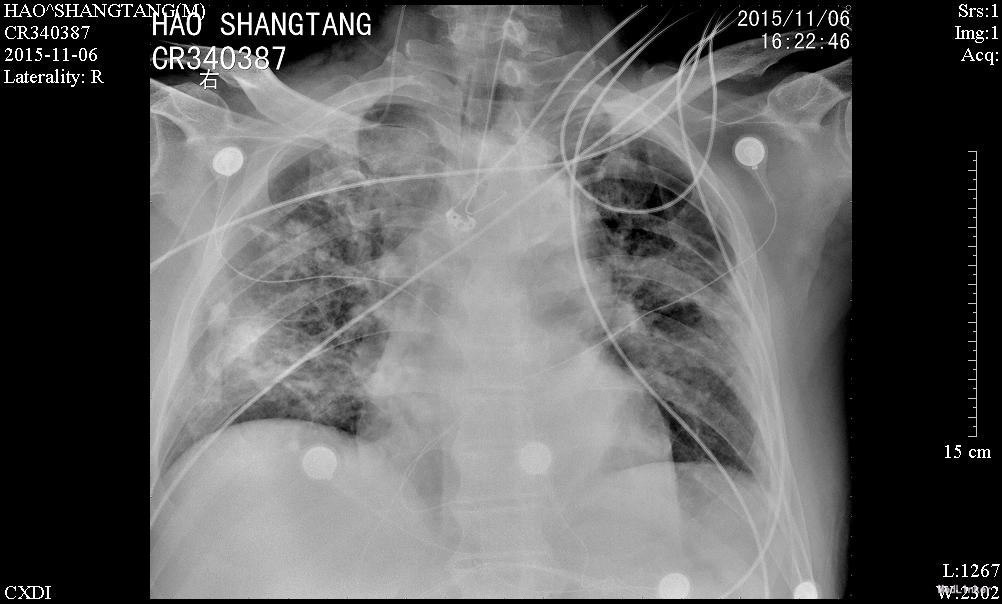

男,82岁,已婚,因“肢体抽搐伴意识障碍1天“入我院神经内科,因肺部感染加重10天后转入呼吸内科

患者嗜睡,呼之可稍睁眼,未发作肢体抽搐,右下肢水肿好转,鼻饲饮食,经口气管插管,可吸出少量痰,留置导尿。查体:双肺呼吸音稍粗,可及少量啰音,专科查体:嗜睡,呼之可睁眼,双侧瞳孔等大等圆,直径约2mm,双侧直接、间接对光反射迟钝,玩偶眼(+),双侧额纹对称,鼻唇沟对称,口角无歪斜;肌力检查不配合,粗侧右侧肌力3-4级、左侧肌力4-5级;双侧肱二头肌腱反射+,双侧膝腱反射+,双侧跟腱反射+;双侧Babinski征(-);颈软无抵抗,Kernig征(-),Brudzinski征(-)。双下肢未见明显水肿。

入神经内科经舒普深抗感染及抗癫痫等治疗,无明显癫痫,但肺部感染加重,查见广泛耐药鲍曼不动杆菌及铜绿假单胞菌感染,转入呼吸科后给予美平联合舒普深治疗,1周后成功拔管脱机,2周后体温完全正常,转入康复科继续治疗